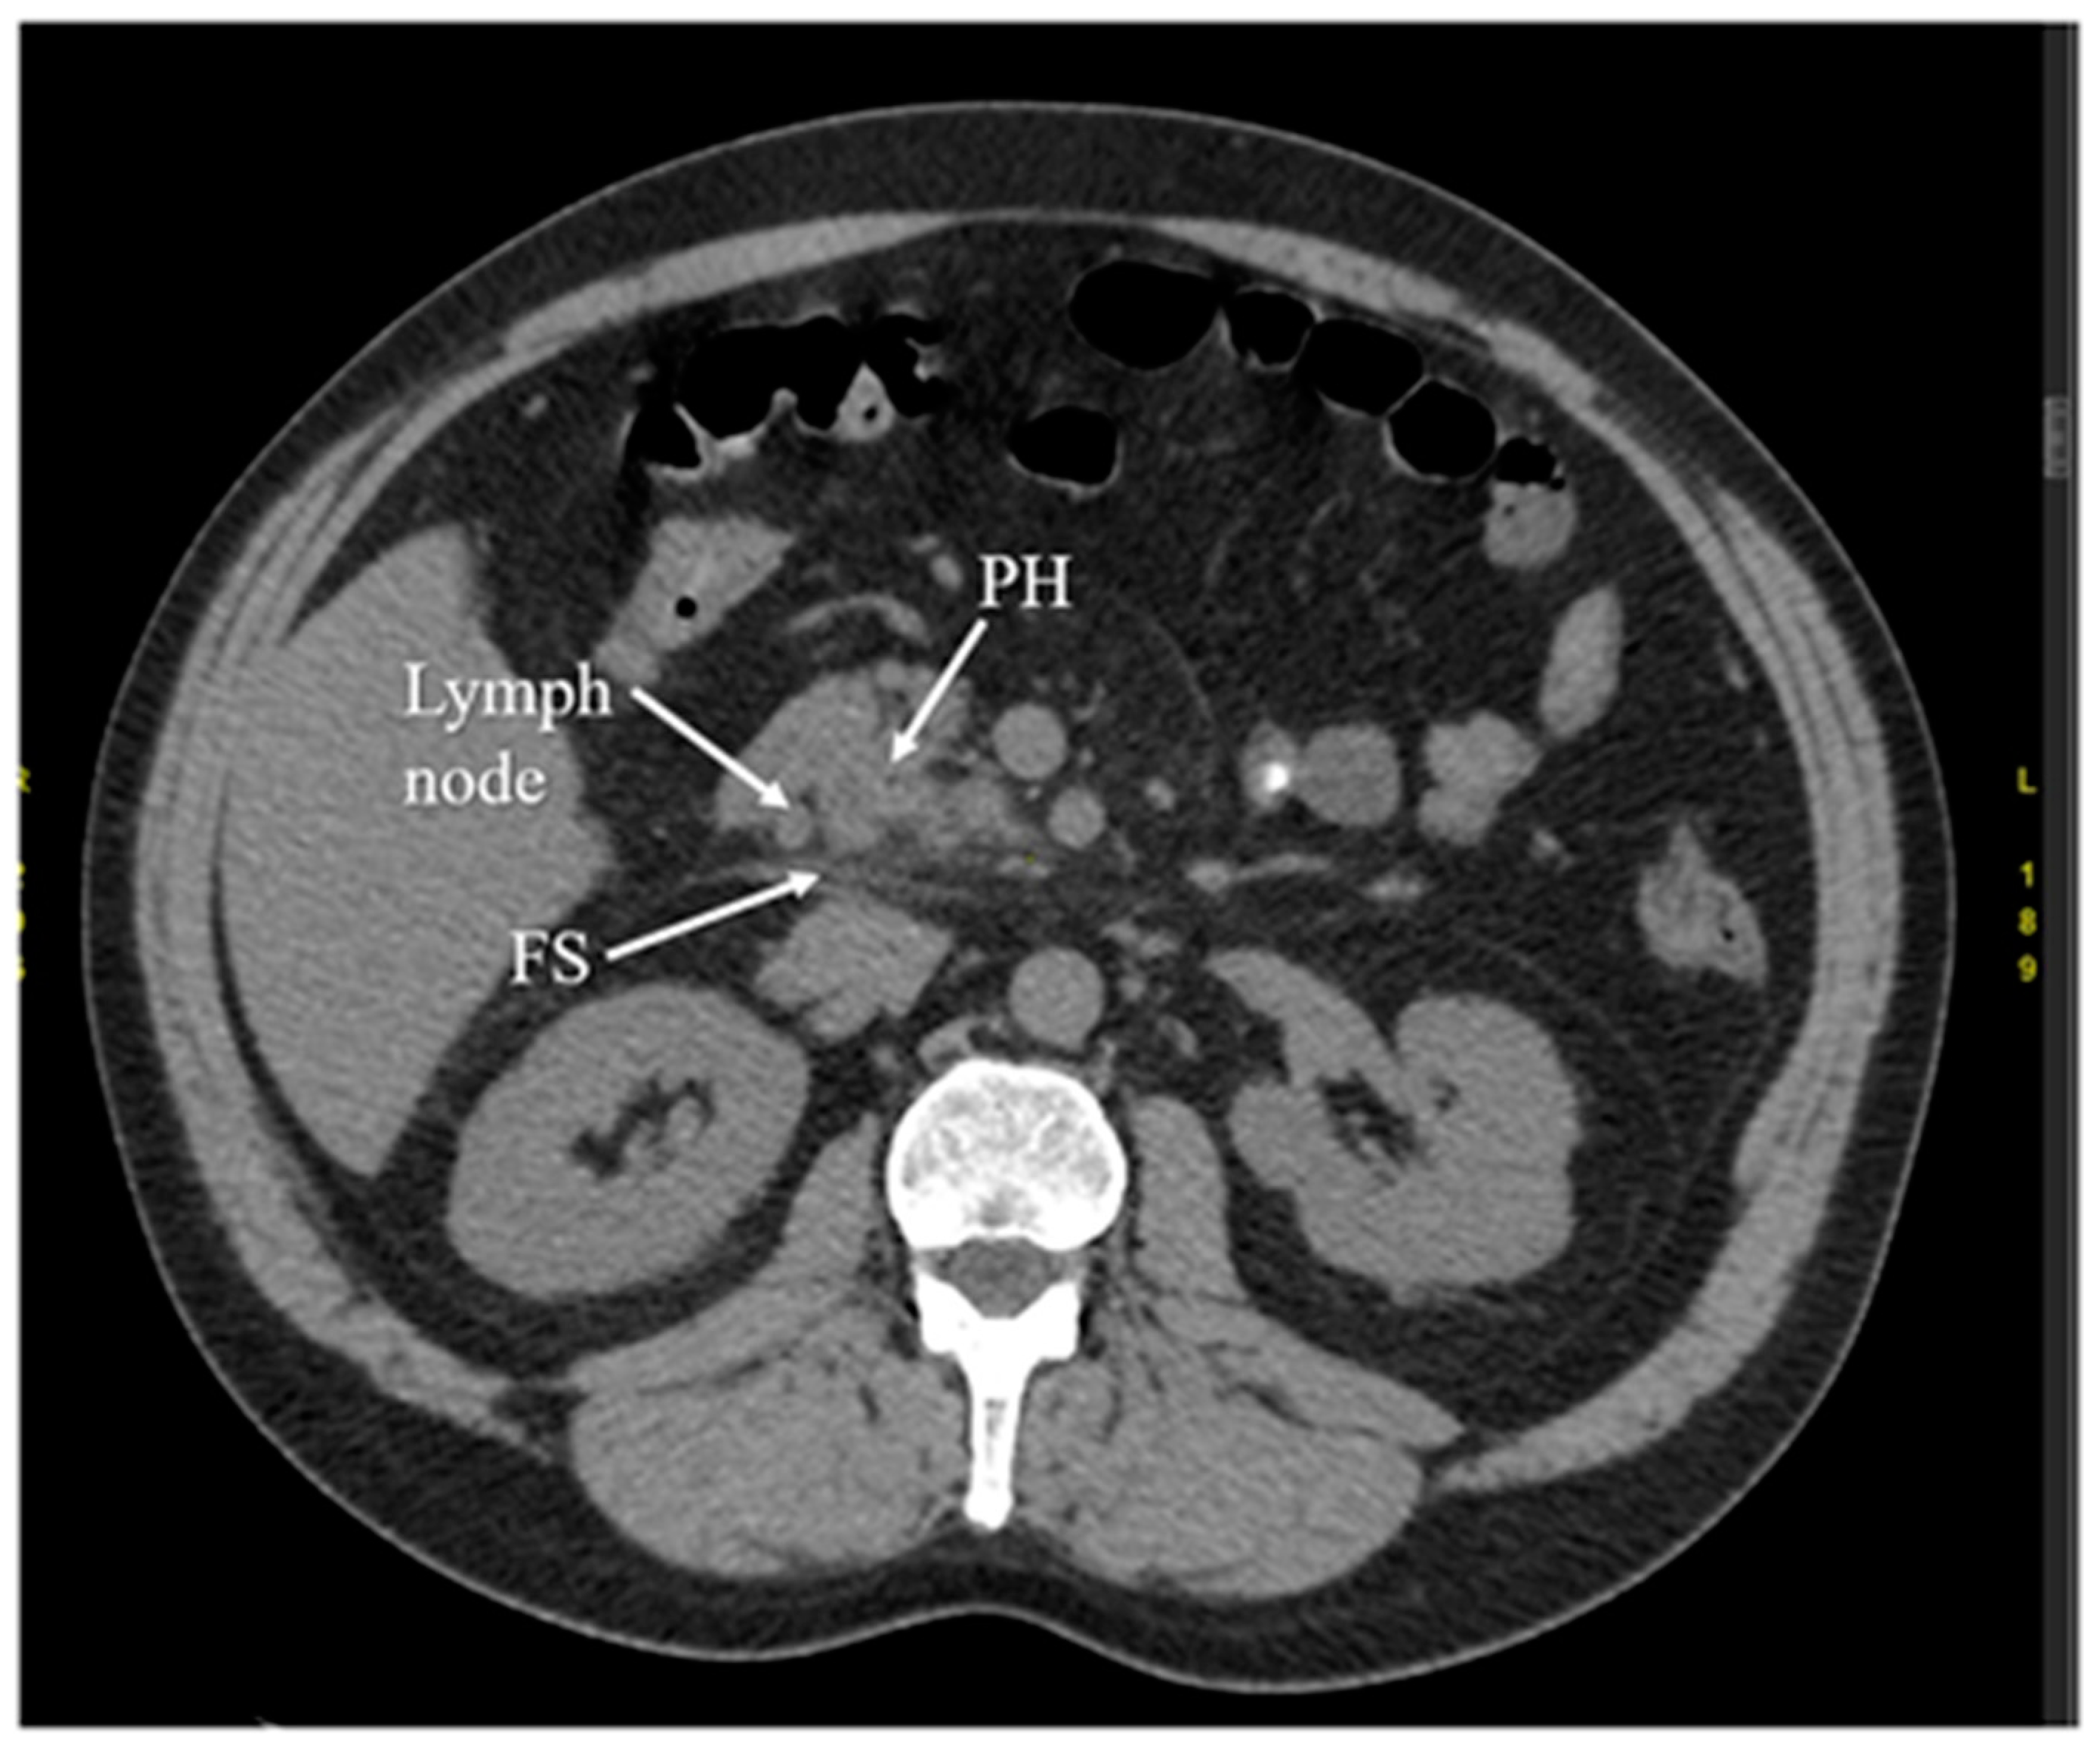

3.5. Computed Tomography

- Raghuwanshi, S.; Gupta, R.; Vyas, M.M.; Sharma, R. CT evaluation of acute pancreatitis and its prognostic correlation with CT severity index. J. Clin. Diagn. Res. 2016, 10, TC06. [Google Scholar] [CrossRef]

- Balthazar, E.J. Acute pancreatitis: Assessment of severity with clinical and CT evaluation. Radiology 2002, 223, 603–613. [Google Scholar] [CrossRef]